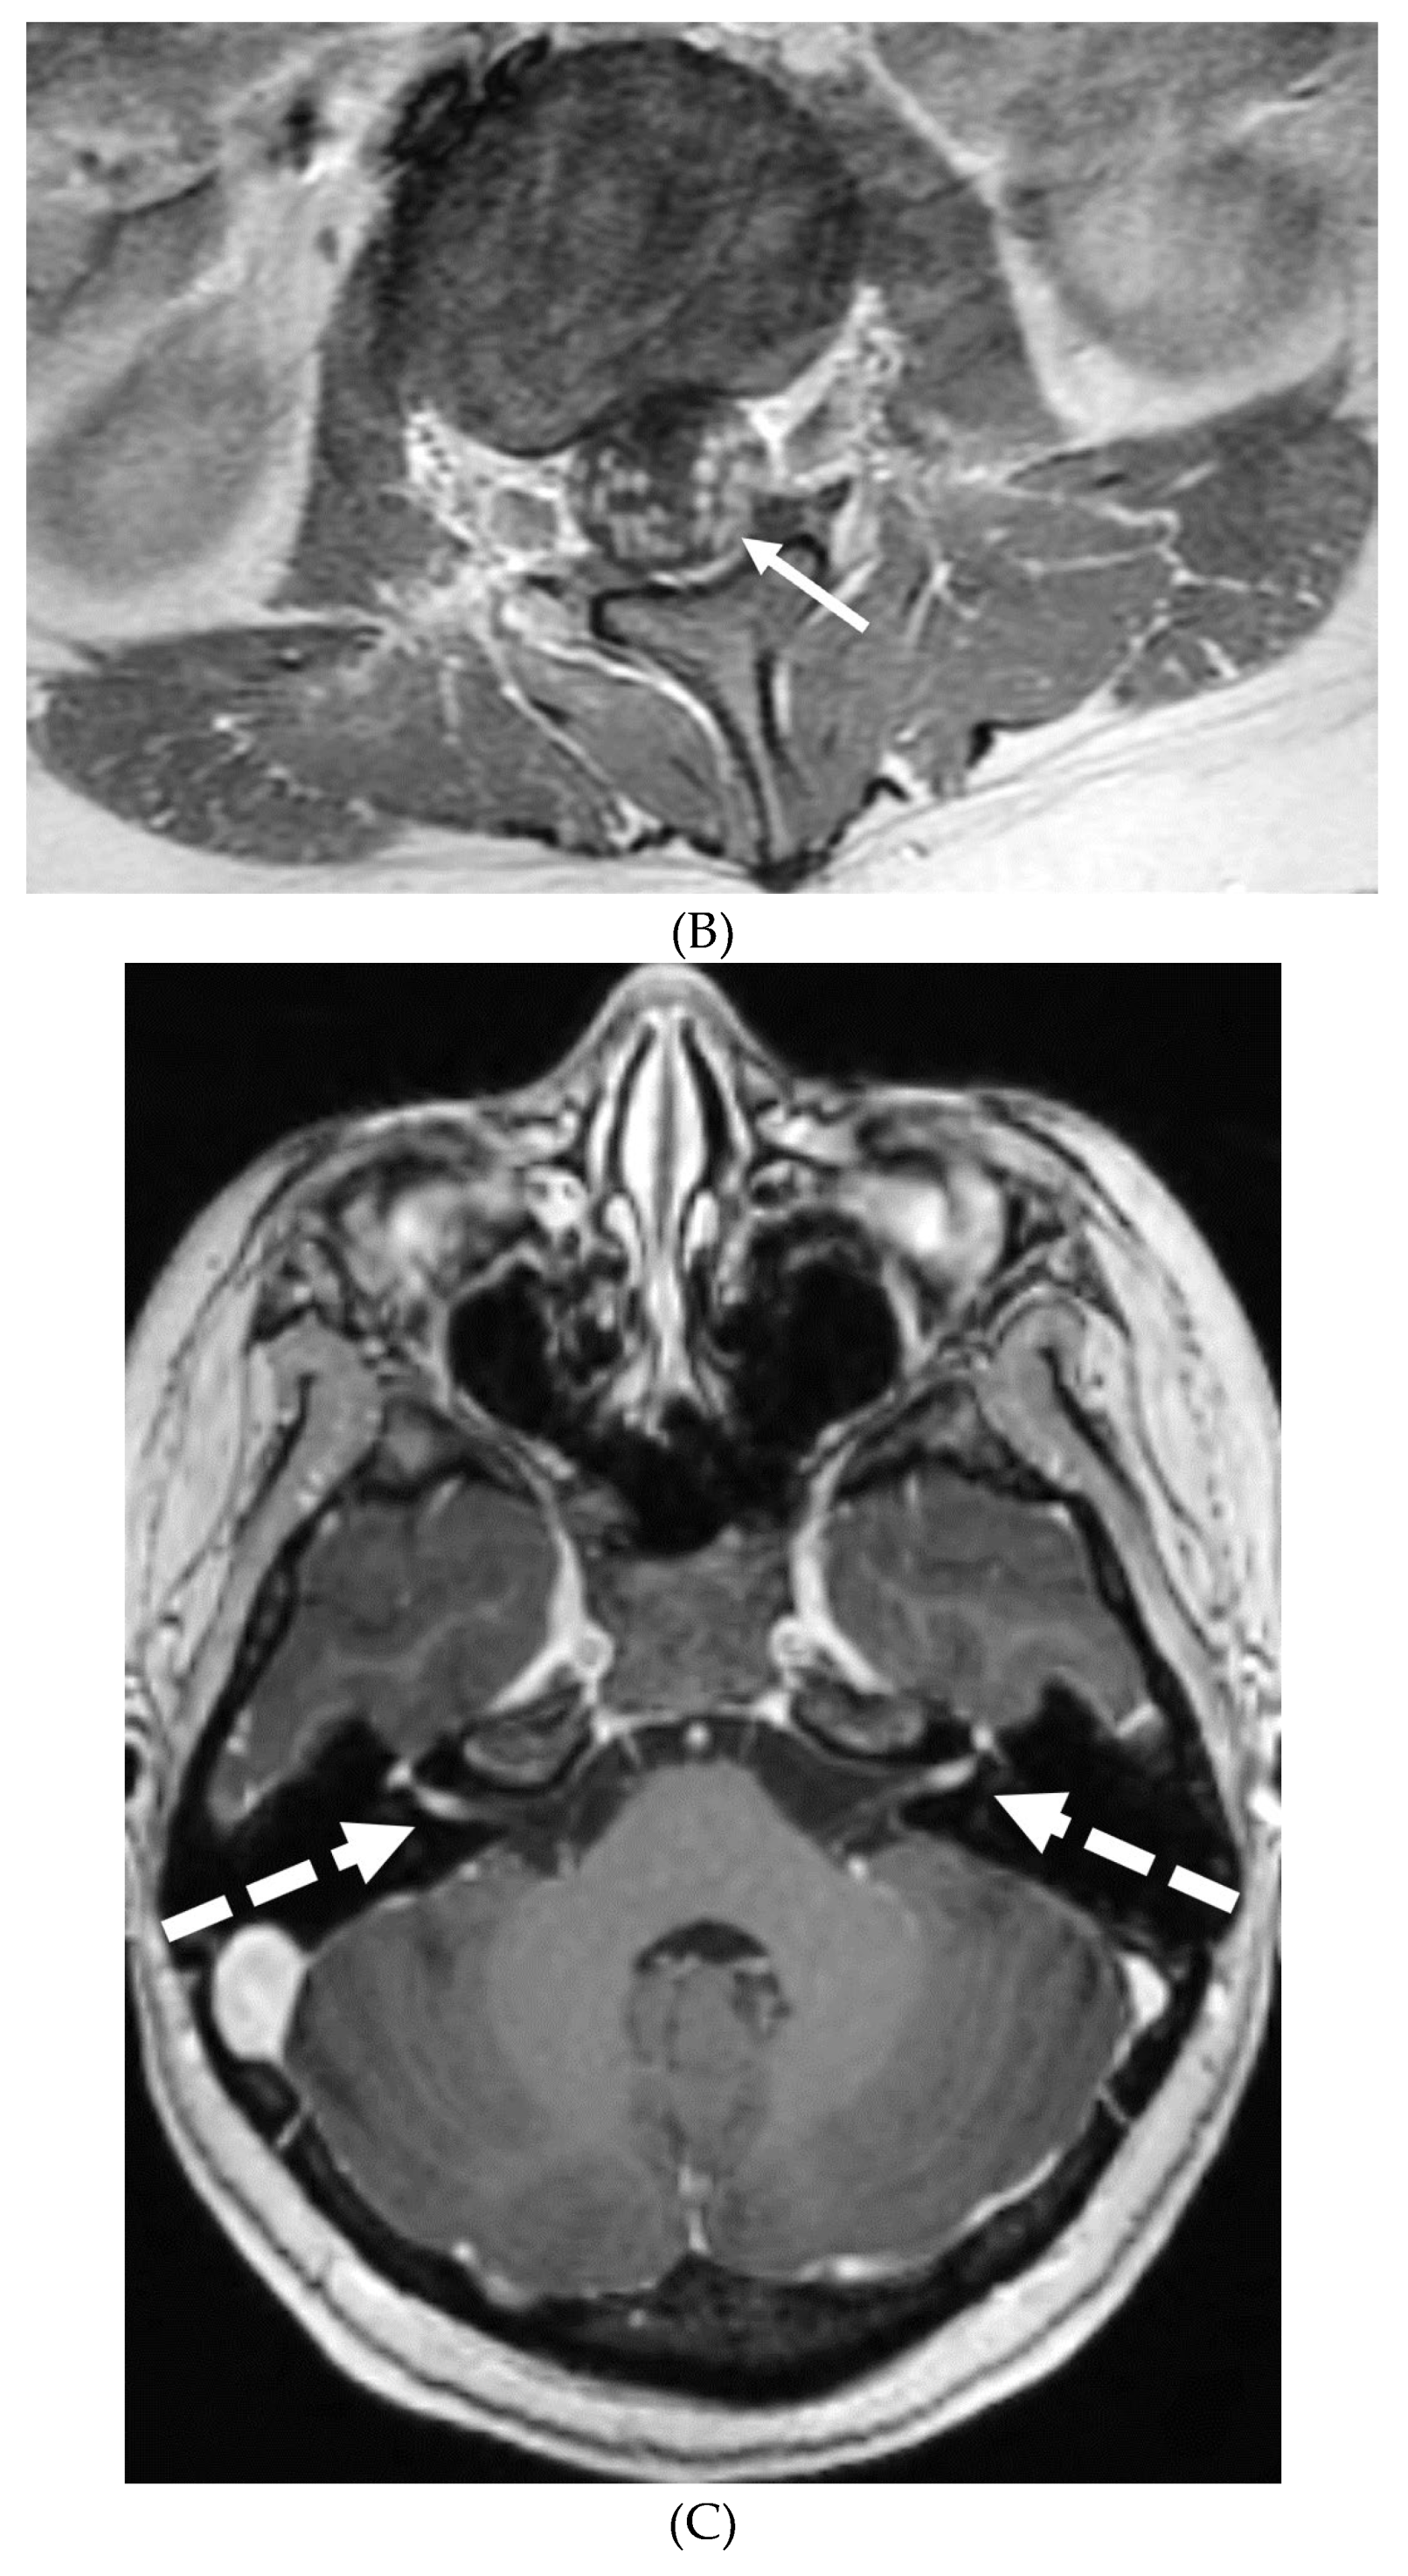

- Peterson EE, Riley BL, Windsor RB. Pediatric Intracranial Hypotension and Post-Dural Puncture Headache. Semin Pediatr Neurol. 2021 Dec;40:100927. Epub 2021 Sep 3. PMID: 34749914. [CrossRef]

- Schievink WI, Maya MM, Louy C, Moser FG, Sloninsky L. Spontaneous intracranial hypotension in childhood and adolescence. J Pediatr. 2013 Aug;163(2):504-10. Epub 2013 Feb 28. PMID: 23453548. [CrossRef]

- Shah LM, McLean LA, Heilbrun ME, Salzman KL. Intracranial hypotension: improved MRI detection with diagnostic intracranial angles. AJR Am J Roentgenol. 2013 Feb;200(2):400-7. PMID: 23345364. [CrossRef]

- Yuh EL, Dillon WP. Intracranial hypotension and intracranial hypertension. Neuroimaging Clin N Am. 2010 Nov;20(4):597-617. PMID: 20974378. [CrossRef]

- Medina JH, Abrams K, Falcone S, Bhatia RG. Spinal imaging findings in spontaneous intracranial hypotension. AJR Am J Roentgenol. 2010 Aug;195(2):459-64. PMID: 20651205. [CrossRef]